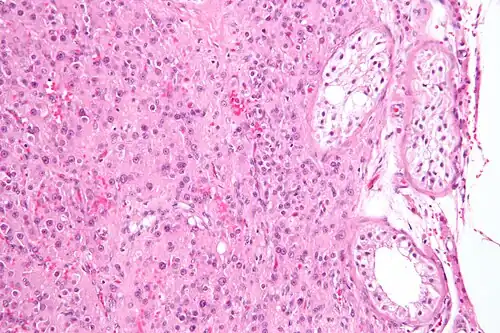

![]() Micrograph showing a cluster of Leydig cells (center of image). H&E stain. | |

Leydig cells, also known as interstitial cells of the testes and interstitial cells of Leydig, are found adjacent to the seminiferous tubules in the testicle and produce testosterone in the presence of luteinizing hormone (LH).[1][2] They are polyhedral in shape and have a large, prominent nucleus, an eosinophilic cytoplasm, and numerous lipid-filled vesicles.[3] Males have two types of Leydig cells that appear in two distinct stages of development: the fetal type and the adult type.[4]

The mammalian Leydig cell is a polyhedral epithelioid cell with a single eccentrically located ovoid nucleus. The nucleus contains one to three prominent nucleoli and large amounts of dark-staining peripheral heterochromatin. The acidophilic cytoplasm usually contains numerous membrane-bound lipid droplets and large amounts of smooth endoplasmic reticulum (SER).[5] Besides the abundance of SER with scattered patches of rough endoplasmic reticulum, several mitochondria are also prominent within the cytoplasm. Reinke crystals have lipofuscin pigment and rod-shaped crystal-like structures 3 to 20 micrometres in diameter.[6]